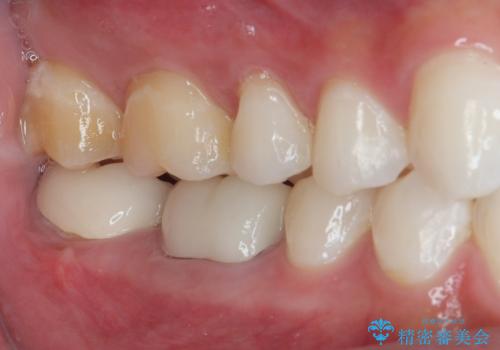

- 歯列矯正後の後戻りのチェックで来院された際に右下に虫歯ができて歯に穴が開いたとのことで来院された患者様です。

虫歯の上に歯茎が覆いかぶさっていたので、レーザーにて歯茎を除去し虫歯が大きいことが予想できたのでラバーダム防湿下で虫歯の除去をしました。

オールセラミッククラウンに適した形に整え、歯と歯茎の間に圧排糸と言われる糸を入れてシリコーン印象材にて型どりをしました。

審美面、機能面共に満足していただけました。

舌側の虫歯が大きかったため歯茎の腫れが心配でしたが腫れもなく経過良好です。